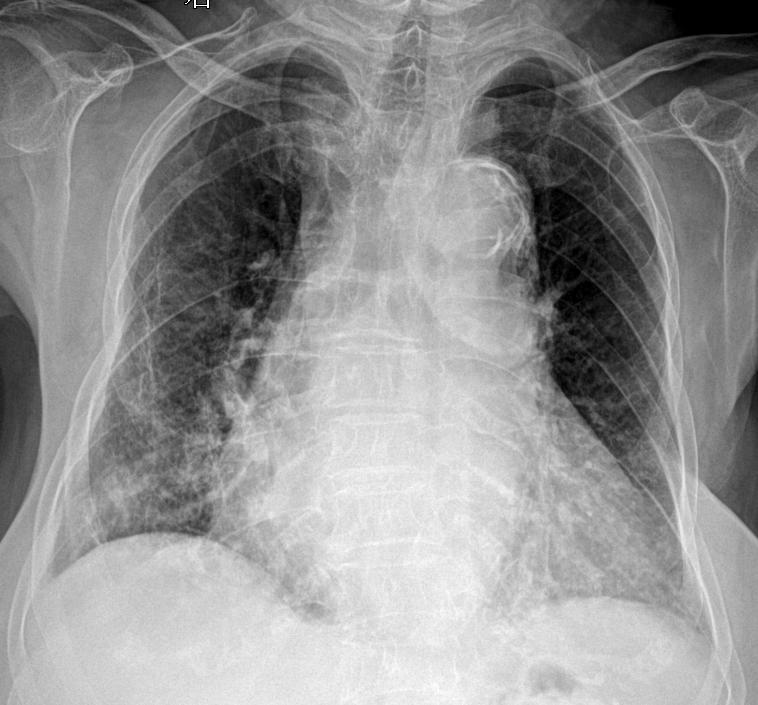

主诉:咳嗽 闷气 男 80y 考虑什么家人们?答案打到评论区